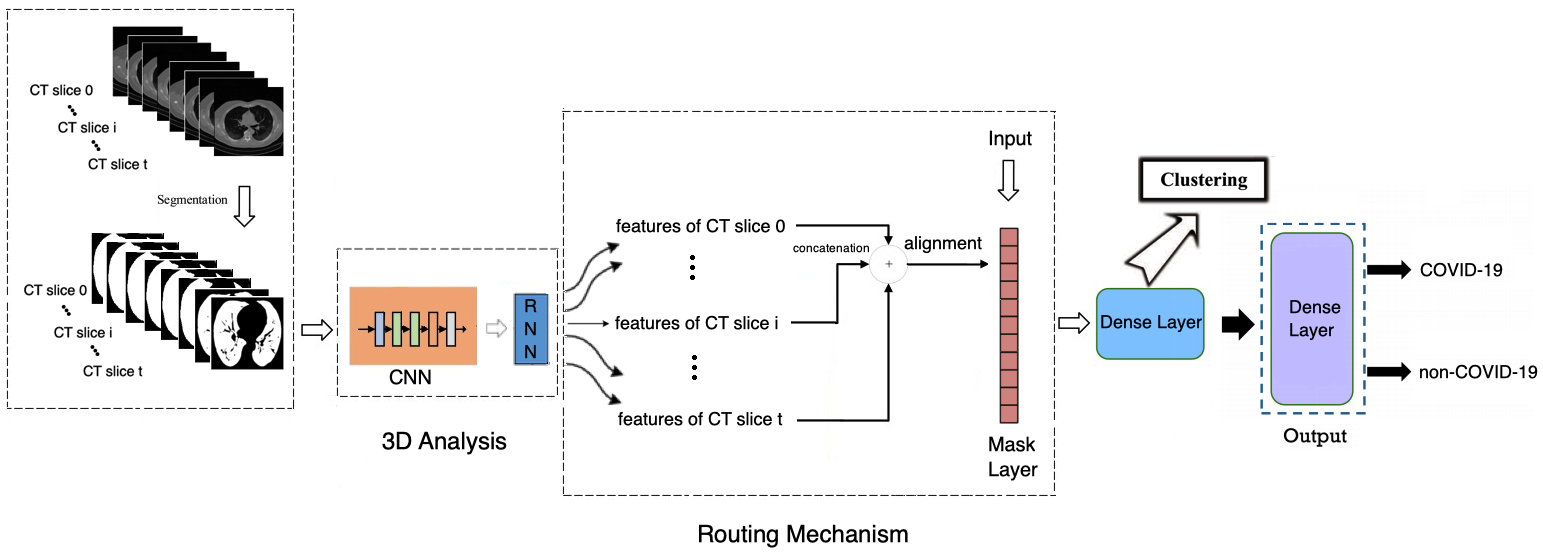

In the paper, we develop a deep neural architecture able to: i) analyze the 3-D CT scan inputs, ii) effectively handle the problem that each CT scan consists of a different number of CT slices and iii) provide a very high performance, when used on COV19-CT-DB and on other public datasets for COVID-19 diagnosis. RoutingAlignCovidNet (RACNet) is a CNN-RNN architecture [14] that is modified to include routing and feature alignment steps that dynamically select the specific RNN outputs to be fed to the dense (fully connected) layers for decision making, i.e., COVID-19 diagnosis.

In the following we propose a CNN-RNN architecture, RoutingAlignClusterNet (RACNet), instead of a 3-D CNN one. By including a Mask Layer after the RNN part, RACNet dynamically selects RNN outputs taking into account the input length, i.e., the number of slices of the analyzed CT scan. This is depicted in Figure 3, where denotes the maximum number of slices that appear among all available chest CT scans; the Mask Layer performs a dynamic routing procedure, as is explained below.

At first all input CT scans are padded to have length (i.e., consist of slices). Then the CNN part performs local, per 2-D slice, analysis, extracting features mainly from the lung regions. The target is to make diagnosis using the whole 3-D CT scan series, similarly to the way medical experts provide the annotation. The RNN part provides this decision, analyzing the CNN features of the whole 3-D CT scan, sequentially moving from slice to slice .

As shown in Figure 3, we get RNN features corresponding to each CT slice, from to . We then concatenate these features and feed them to the Mask Layer. The original (before padding) length of the input series is transferred from the input to the Mask Layer to inform the routing process. During RACNet training, the routing mechanism performs dynamic selection of the RNN outputs/features. In particular, it selects as many of them as denoted by the length of the input series, keeping their values, while zeroing the values of the rest RNN outputs. In this way, it is routing only the selected ones into the following dense layer.

This can be done: a) by selecting the first RNN outputs, or, b) through an ’alignment’ step, i.e., by first placing the RNN outputs in equidistant positions in and by then placing the remaining outputs in the in-between positions; the Mask gets their positions and performs routing of the respective RNN outputs to the following dense layer.

This dense layer learns to extract high level information from the concatenated RNN outputs. During training, we update only the weights that connect the dense layer neurons with the RNN outputs routed in the concatenated vector by the Mask layer. The remaining weights are updated whenever (i.e., in another input CT scan) respective RNN outputs are selected in the concatenated vector by the Mask Layer. Loss function minimization is performed, as in networks with dynamic routing, by keeping the weights that do not participate in the routing process constant, and ignoring links that correspond to non-routed RNN outputs.

The final output layer follows, using a softmax activation function and providing the final COVID-19 diagnosis.